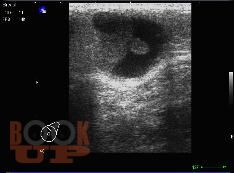

Методические аспекты ультразвукового исследования злокачественных образований молочной железы

В учебном пособии представлены методические подходы к ультразвуковому исследованию молочных желез, определены возможности ультразвукового метода исследования в выявлении и дифференциации вида злокачественных образований молочных желез, проведена оценка его роли и места в диагностическом алгоритме на основании изучения литературных данных и собственных наблюдений.